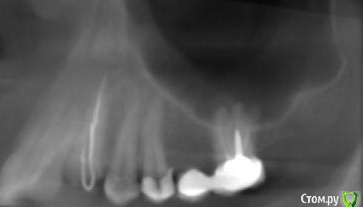

platerx Опубликовано 21 декабря, 2015 Поделиться Опубликовано 21 декабря, 2015 (изменено) Всем доброго времени суток.У меня есть пара вопросов: 1. Что можно сделать с зубом 2.7 История зуба такова:Зуб был сильно разрушен, но мне предложили попробовать пролечить его. Прочистили каналы, я некоторое время ходил с лекарством в зубе. Затем запломбировали каналы и поставили вкладку и коронку (консоль). Это было 2,5 года назад.С тех пор зуб меня иногда немного беспокоил, вызывая некоторый дискомфорт, но я не сильно обращал внимание. В последнее время он стал беспокоить сильнее: время от времени вызывает тянущие и распирающие ощущения, которые усиливаются при нажатии. Слегка побаливает десна и небо с внутренней стороны. Периодически ощущения пропадают. Прикладываю срезы КТ этого зуба. Что можно сделать с этим зубом ? Можно ли извлечь вкладку и перелечить каналы ? 2. При депульпировании зуба 2.4 врач не промывал каналы гипохлоритом (только хлоргексидином), после чего запломбировал их. Это нормально или стоит переделать? На зубе сейчас временная пломба, по прошествии 6 дней зуб не беспокоит. При постукивании есть небольшие неприятные ощущения. Изменено 21 декабря, 2015 пользователем platerx Ссылка на комментарий

DmitrySH Опубликовано 21 декабря, 2015 Поделиться Опубликовано 21 декабря, 2015 Добрый вечер.27. Есть очаг воспаления на одном из корней. Нужно снять коронку, оценить объём тканей. Если все ок, то извлечение вкладки и ревизия каналов.24. Сложно дать однозначный ответ. После выяснения ситуации с 27 планировать имплантацию в области 26 или 26, 27 (если с 27 все плохо) Ссылка на комментарий